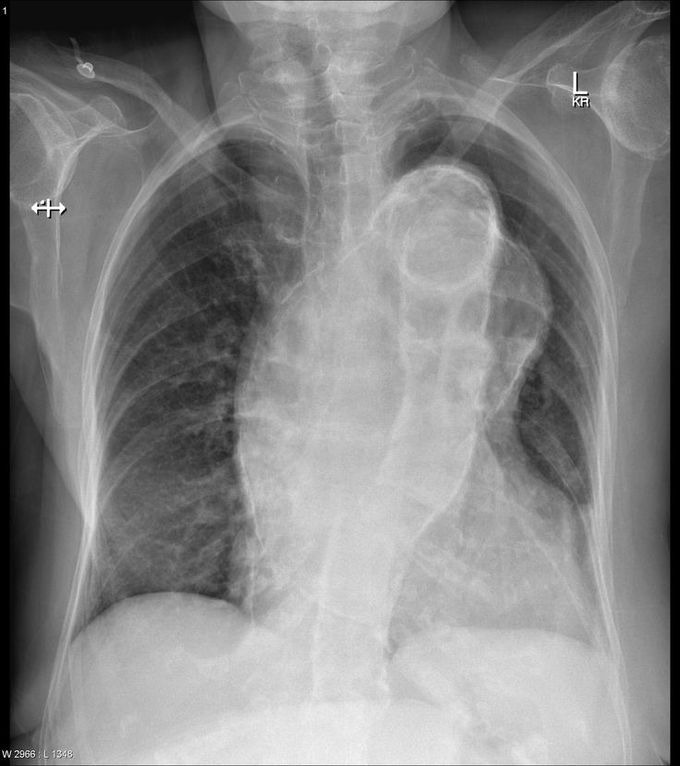

What is you spot diagnosis? Drop comment below. Answer coming soon...

Answer: Horacic aneurysms!!! Horacic aneurysms are often identified incidentally on imaging of the chest. A symptomatic presentation may be due to mass effect on airway or oesophagus. Alternatively, they may present due to a complication, including rupture, aorto-bronchial or aorto-oesophageal fistulae.